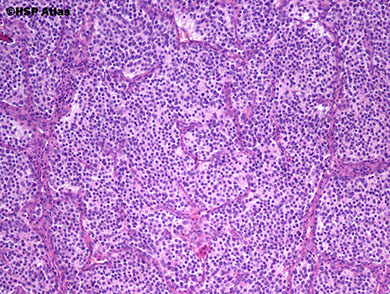

Olfactory neuroblastoma / Esthesioneuroblastoma

neural crest origin, from NE cells of olfactory mucosa covering superior 1/3 of nasal septum, crib plate, superior turbinate

- round blue cell tumor, can have true and pseudorosettes

- F>M, peaks in 2nd and 6th decades of life, though can be found at any age and causes nasal obstruction, nasal bleeding, loss of smell, headaches

Micro: more differentiated tumors c lymphocytic-appearing infiltrate in a mesh of neuroglial fibers that appears lobular on low power

- can have Homer-Wright rosettes

- low mits, and no necrosis or pleomorphism in low-grade tumors; high grade lesions c less neurofibrillary background and can have Flexner-Wintersteiner rosettes (true neural rosettes)

IHC: (+) calretinin, SYN (10/10), NSE

- neg: S100 (only pos stromal cells, can be focal), EMA, CK (can be focal), EBV

DDx: sinonasal undifferentiated carcinoma (diffuse CK and EMA pos)

Tx: surgery and radiation

Genes: does not have 11:22 translocation

Px: depends of stage (up to 2/5 met, fairly good if not invasive)

Olfactory neuroblastoma (esthesioneuroblastoma)